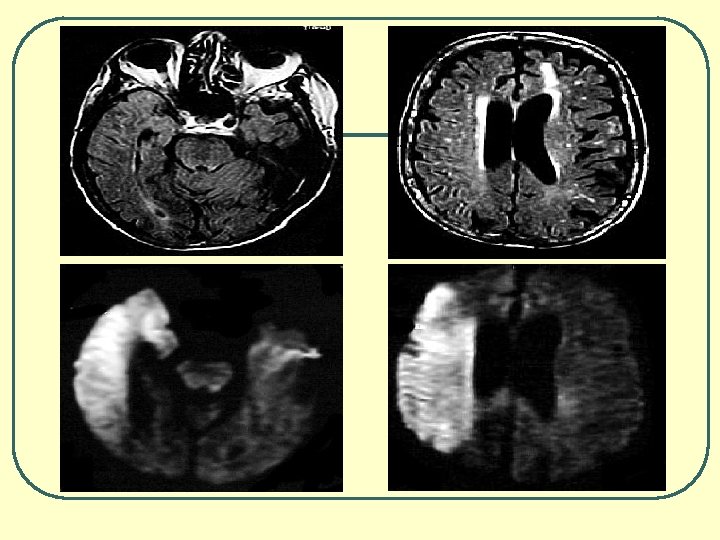

Vantagens da RM • Capacidade multiplanar • Melhor caracterização da lesão tecidual • Quanto ao tipo • Quanto à gravidade • Quanto à localização • Quanto à extensão • Melhor visualização do tronco cerebral • Angiografia • Difusão e Perfusão • Espectroscopia Programa de Educação Médica Continuada do CREMESP

CT - Sangue

AVCH - Hemorragia Intraparenquimatosa Espontânea • Hipertensão arterial • Não baixar PAS<180, PAD<105, PAM<120 mm. Hg • Se PA Acima, baixar apenas 20% dos valores • Corrigir hipertermia e alterações da glicemia • Monitorar Pressão Intracraniana • Não usar corticóides – hiperventilação e manitol • Coma barbitúrico • Profilaxia da hemorragia digestiva do estresse • CONSIDERAR CIRURGIA Programa de Educação Médica Continuada do CREMESP